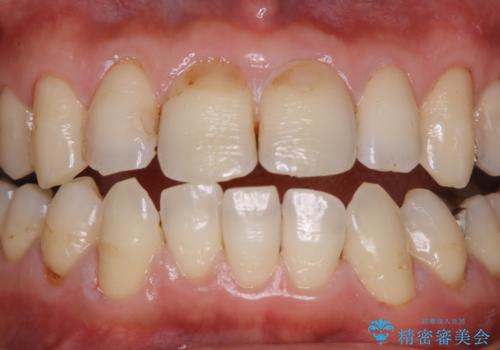

歯の表面に、茶色く色が残っている所がありますが、これは詰め物の変色の所と、虫歯になっている所です。以前に、CR(コンポジットレジン)による虫歯治療がされています。

CRは経年的劣化や、着色してしまうことがあります。PMTCでクリーニングを行うと、古いCRが目立つことがあるため、気になる際は詰め替えを行います。

茶色くなっている部分が、着色なのか、劣化なのか、虫歯によるものなのかは判別が難しいことがあります。そのため、定期的にPMTCを行うことで状態の確認が的確に行えます。